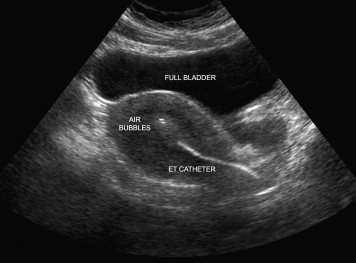

Embryo Transfer